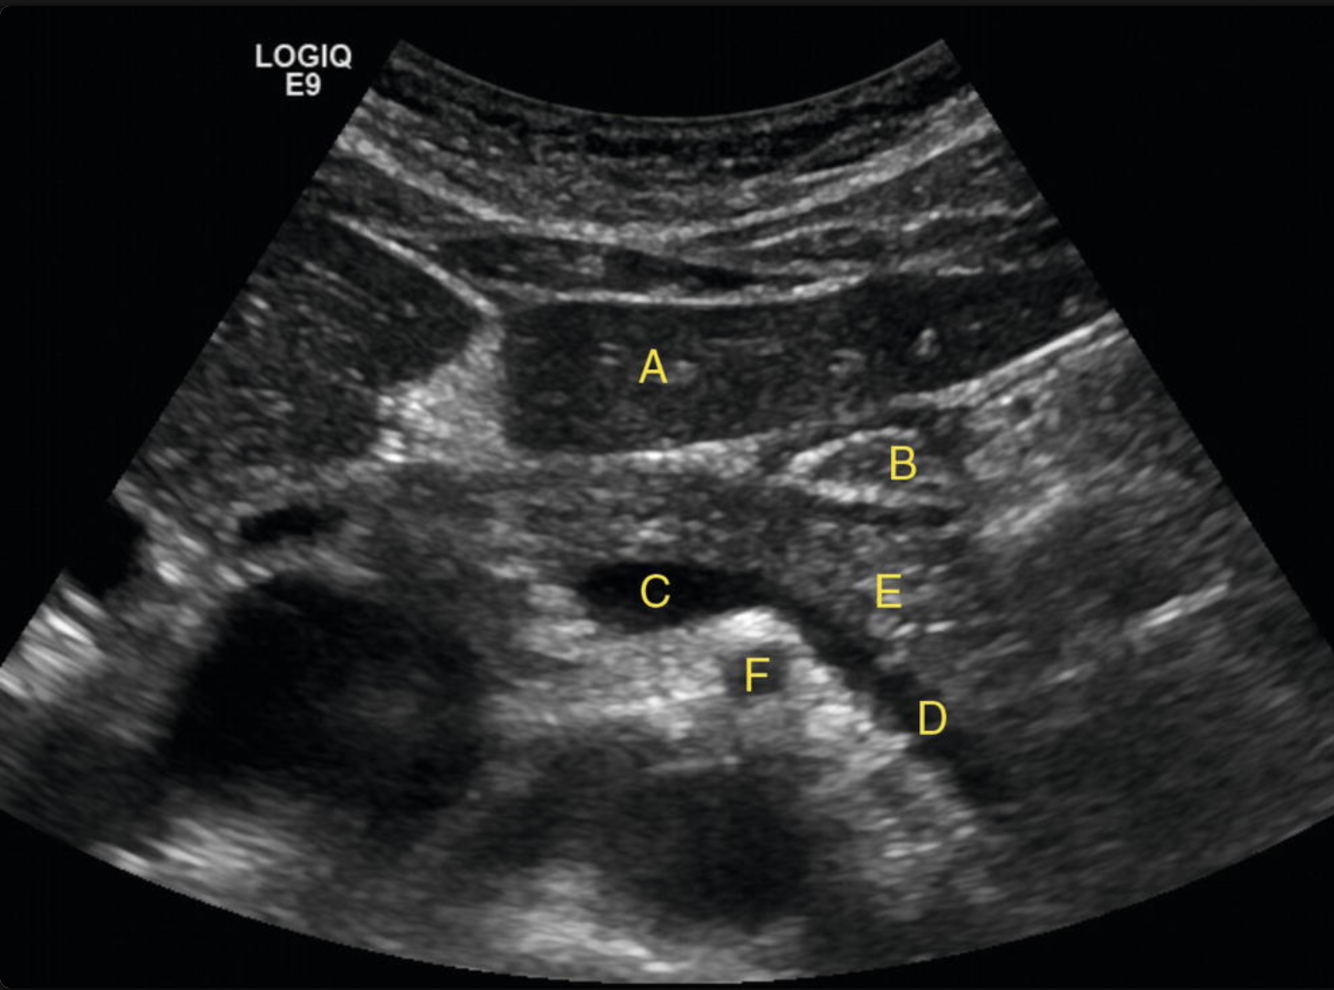

Identify the following structures:

A: liver

B: stomach

C: portosplenic confluence

D: splenic vein

E: pancreatic body

F: SMA